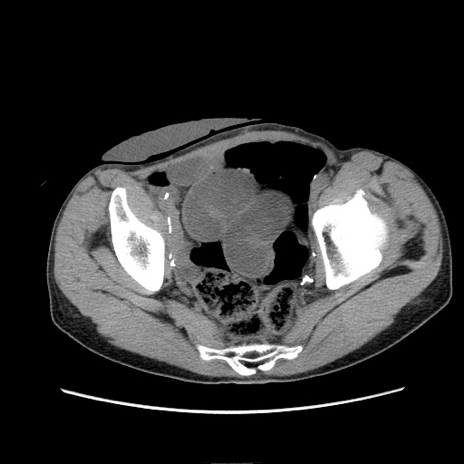

症例11(横断像)

【症例】 60歳代男性

【主訴】 下腹部痛

【現病歴】 本日夜中より下腹部痛の症状認め、受診。

【既往歴】 膀胱癌(膀胱全摘+尿管皮膚瘻術) 、胃癌術後

【身体所見】 BT 35.3℃、PR 58/min、BP 136/98mHg、腹部平坦、軟、腸蠕動音±、ストマ留置あり、左上腹部~正中部に圧痛あり、反跳痛なし。

【データ】WBC 5100、CRP0.01